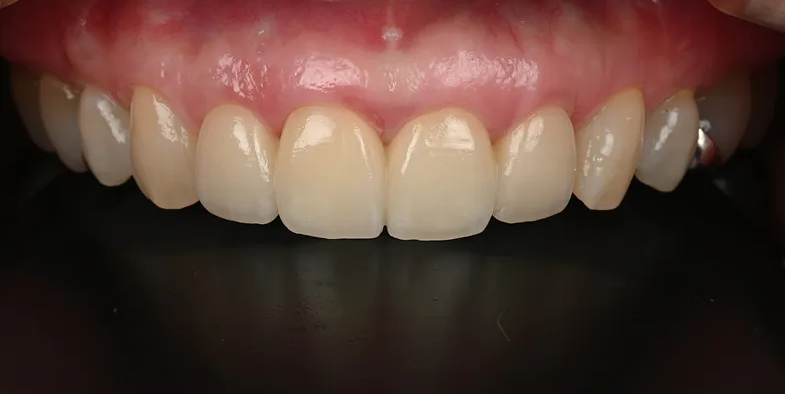

術後

| 治療名 | 右上1、2:前歯インプラント 右上3、左上1:セラミッククラウン |

|---|---|

| 治療説明 | 右上1の歯根破折により抜歯が必要となったため右上1と2の2本にインプラントで歯を補うことを計画しました。右上1に抜歯と同時にインプラントを埋入し、右上2はもともと歯が欠損して歯肉が凹んでいたため、結合組織移植を行い歯肉のボリュームを回復しました。仮歯で歯肉の形を整えてセラミックの歯を装着しました。 |

| 治療回数・期間 | 6ヶ月 |

| 副作用とリスク | 入れ歯やブリッジと比べて治療期間が長くかかることがあります。インプラント手術と結合組織移植は、違和感、痛み、腫れ、出血などが発生する場合があります。一時的なもので、2日〜1週間で治まります。 |

| 料金(税込) | 骨造成:110,000円 インプラント1次手術:220,000円 インプラント2次手術:55,000円 結合組織移植:110,000円 上部構造:220,000円(2本:440,000円 セラミッククラウン:132,000円(2本:264,000円) 合計:1,199,000円 |